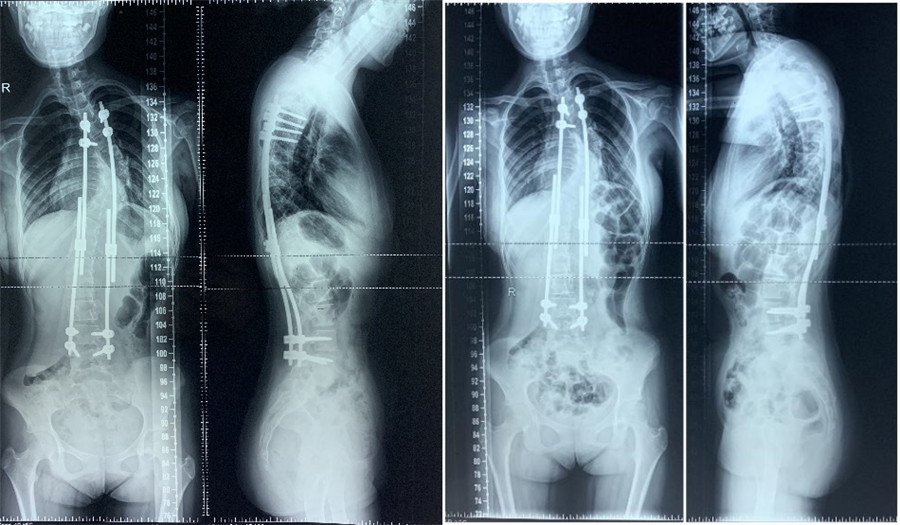

2020年04月彻底根治矫形术胸部Cobb角50°,腰部Cobb角30°站高154cm,坐高122cm